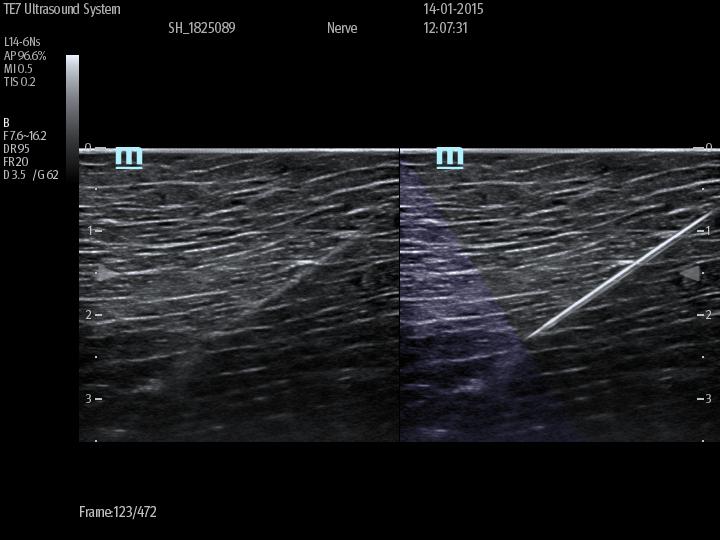

Nåleprogram iNeedle og de automatiserte funksjoner iTouch, Colour Smart Track og iZoom som aktiviseres med en enkel touchbevegelse.